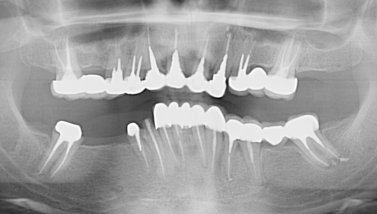

Я живу в маленьком поселке. И то, что предлагают местные врачи, меня не совсем устраивает. Хотелось бы услышать мнение стороннего специалиста. Помогите определиться с планом протезирования?

Комментарий №176991

• Исключительно по ортопантомограмме составить план лечения невозможно. Требуется клинический осмотр и оценка прикуса. Но, совершенно однозначно, перед протезированием требуется терапевтическая реабилитация. Зубы 17-й, 16-й, 15-й, 14-й, 24-й, 25-й, 26-й, 36-й, 35-й, 46-й, 47-й оценить состояние на прицельном рентгеновском снимке. Вероятнее всего потребуется перелечивание корнев читать далее